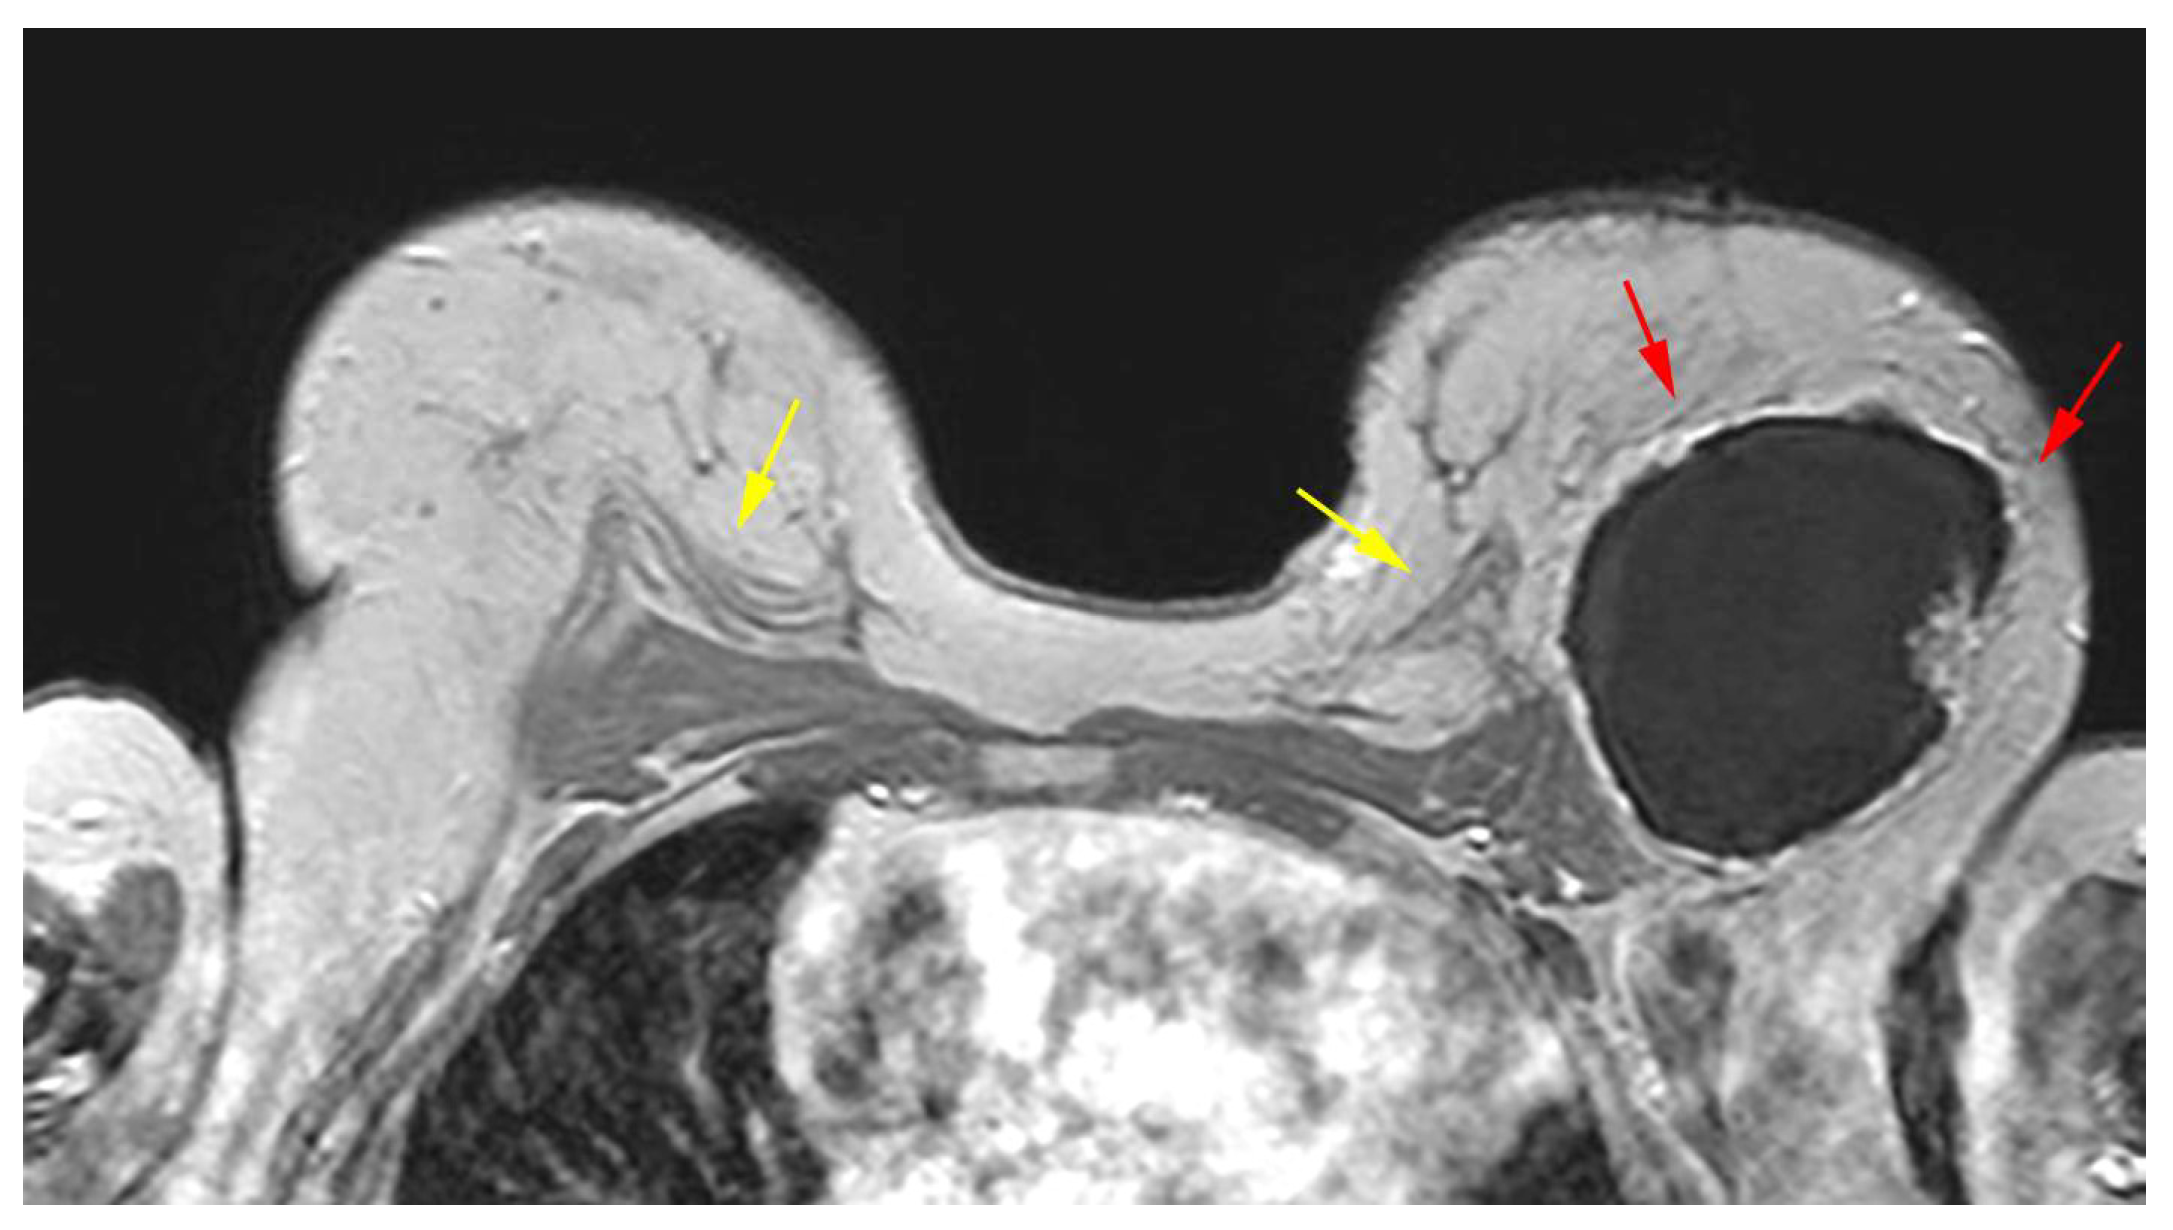

5.2.5. Implant Rupture

5.2.6. Breast Implant Associated Atypical Large Cell Lymphoma (BIA-ALCL)